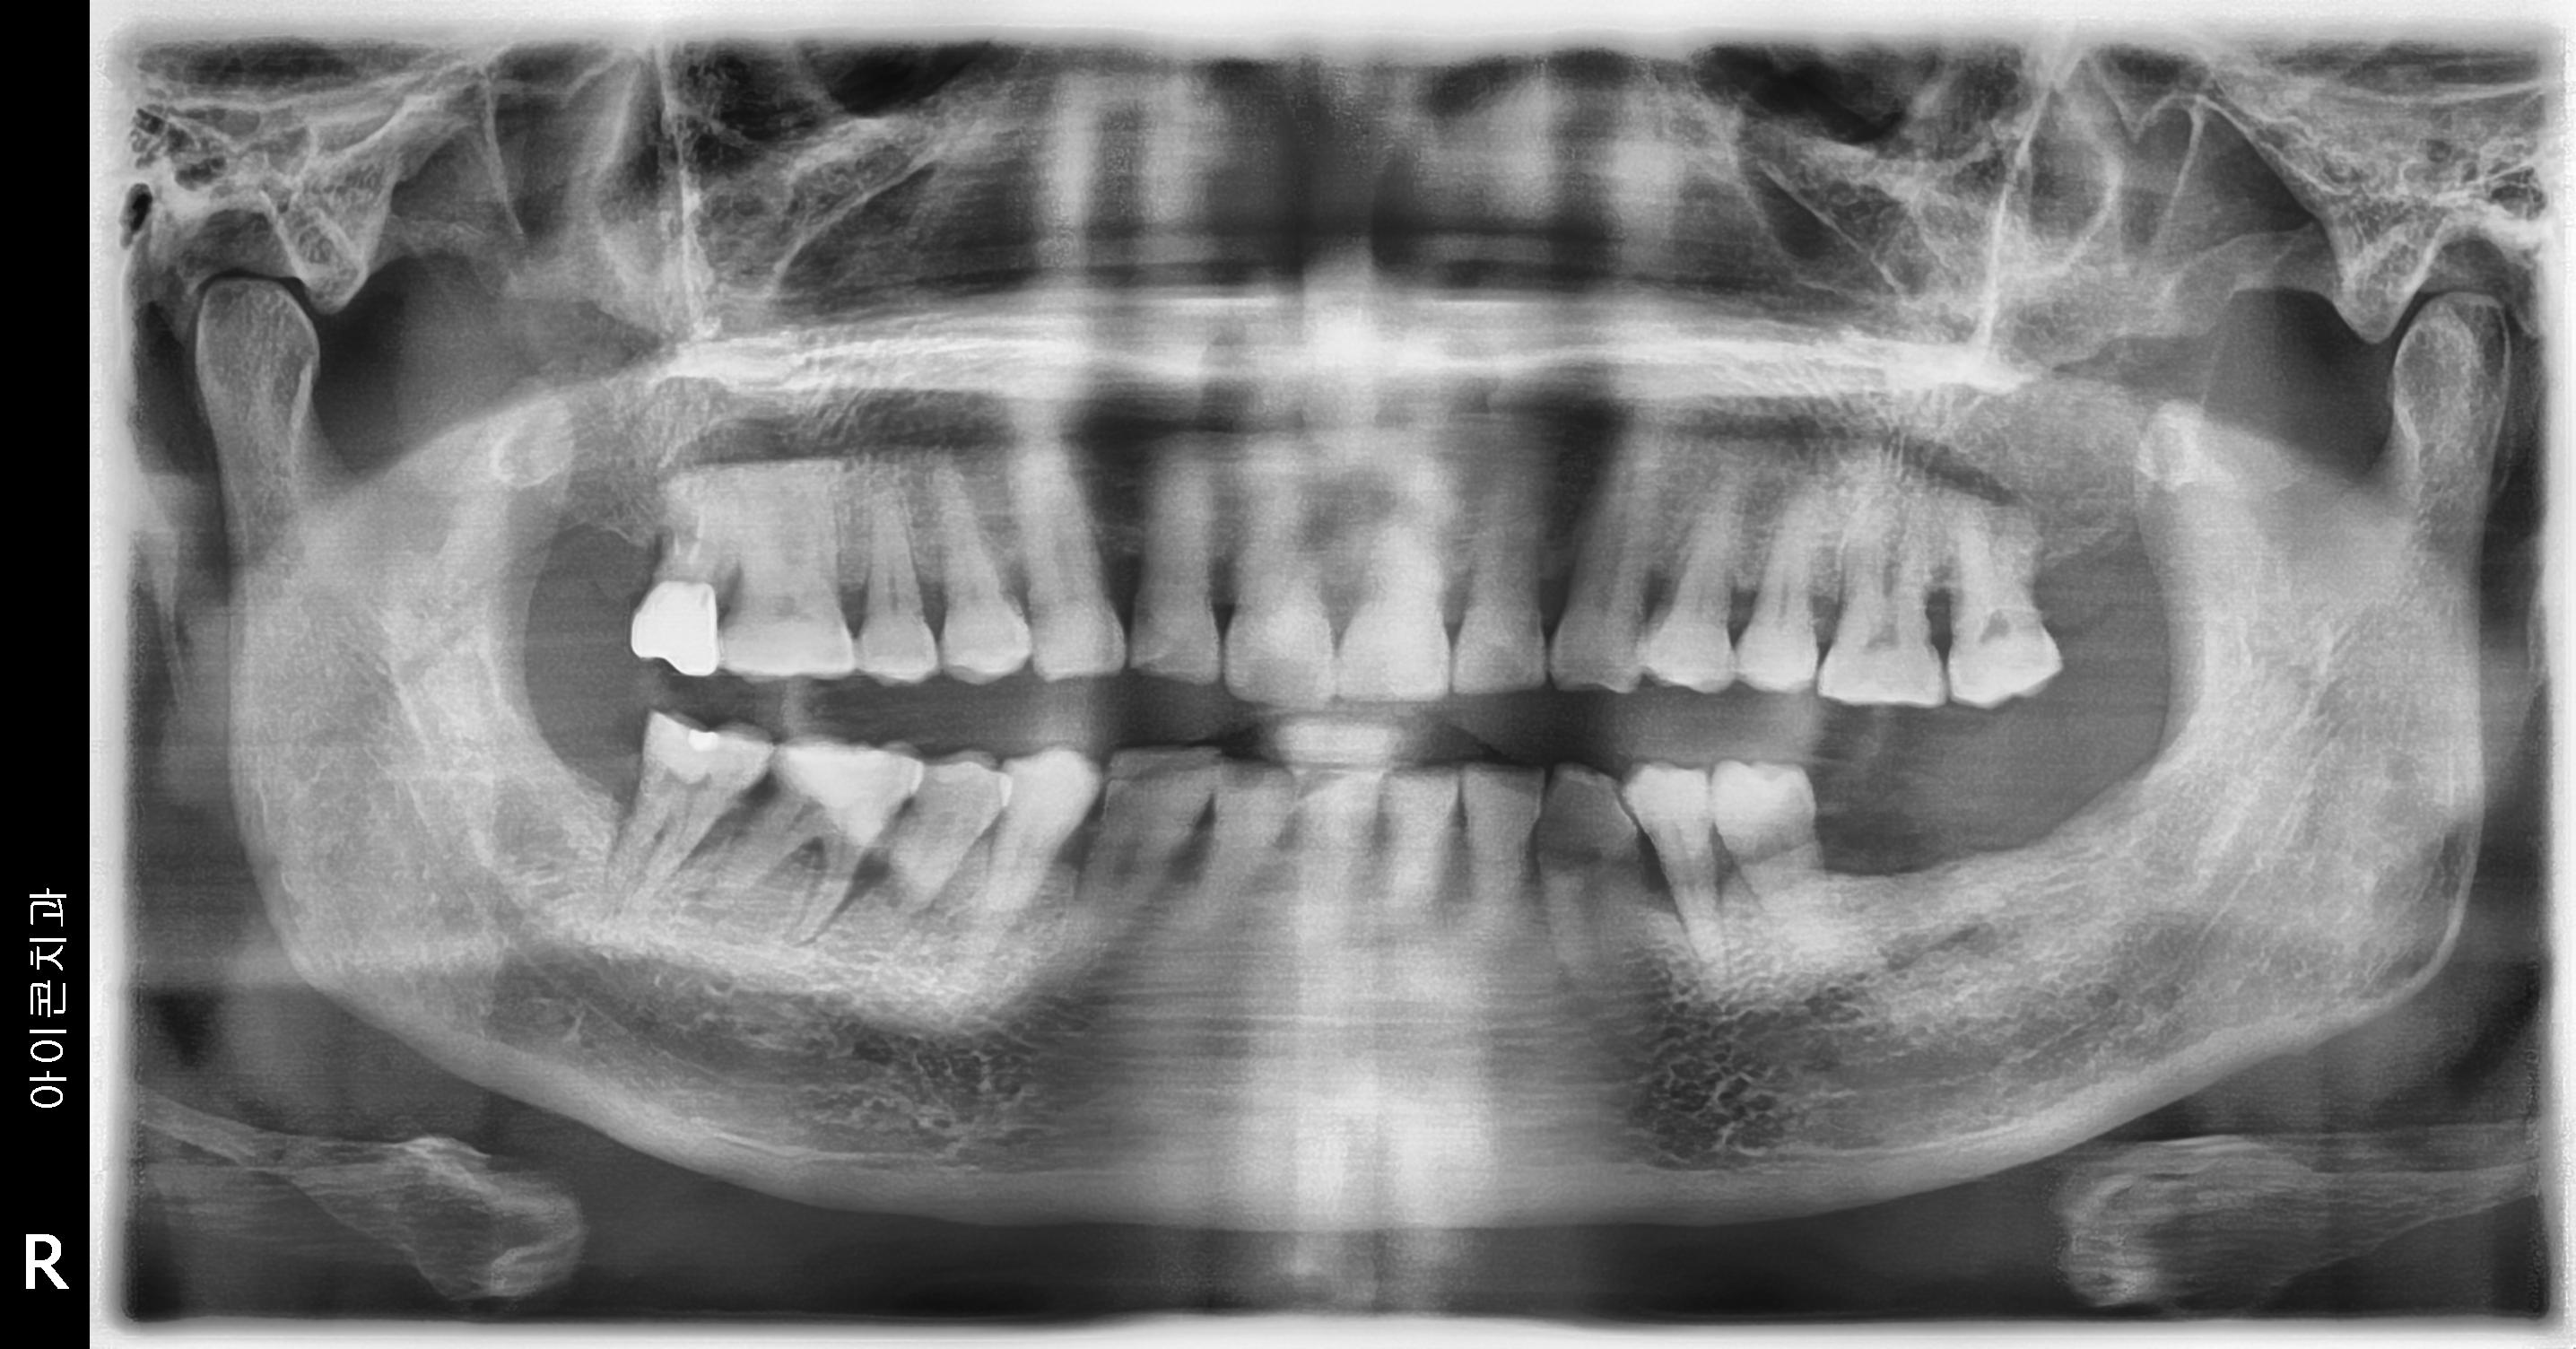

수술 전

수술 후

상하악 구치부 임플란트 식립사례

전후사진